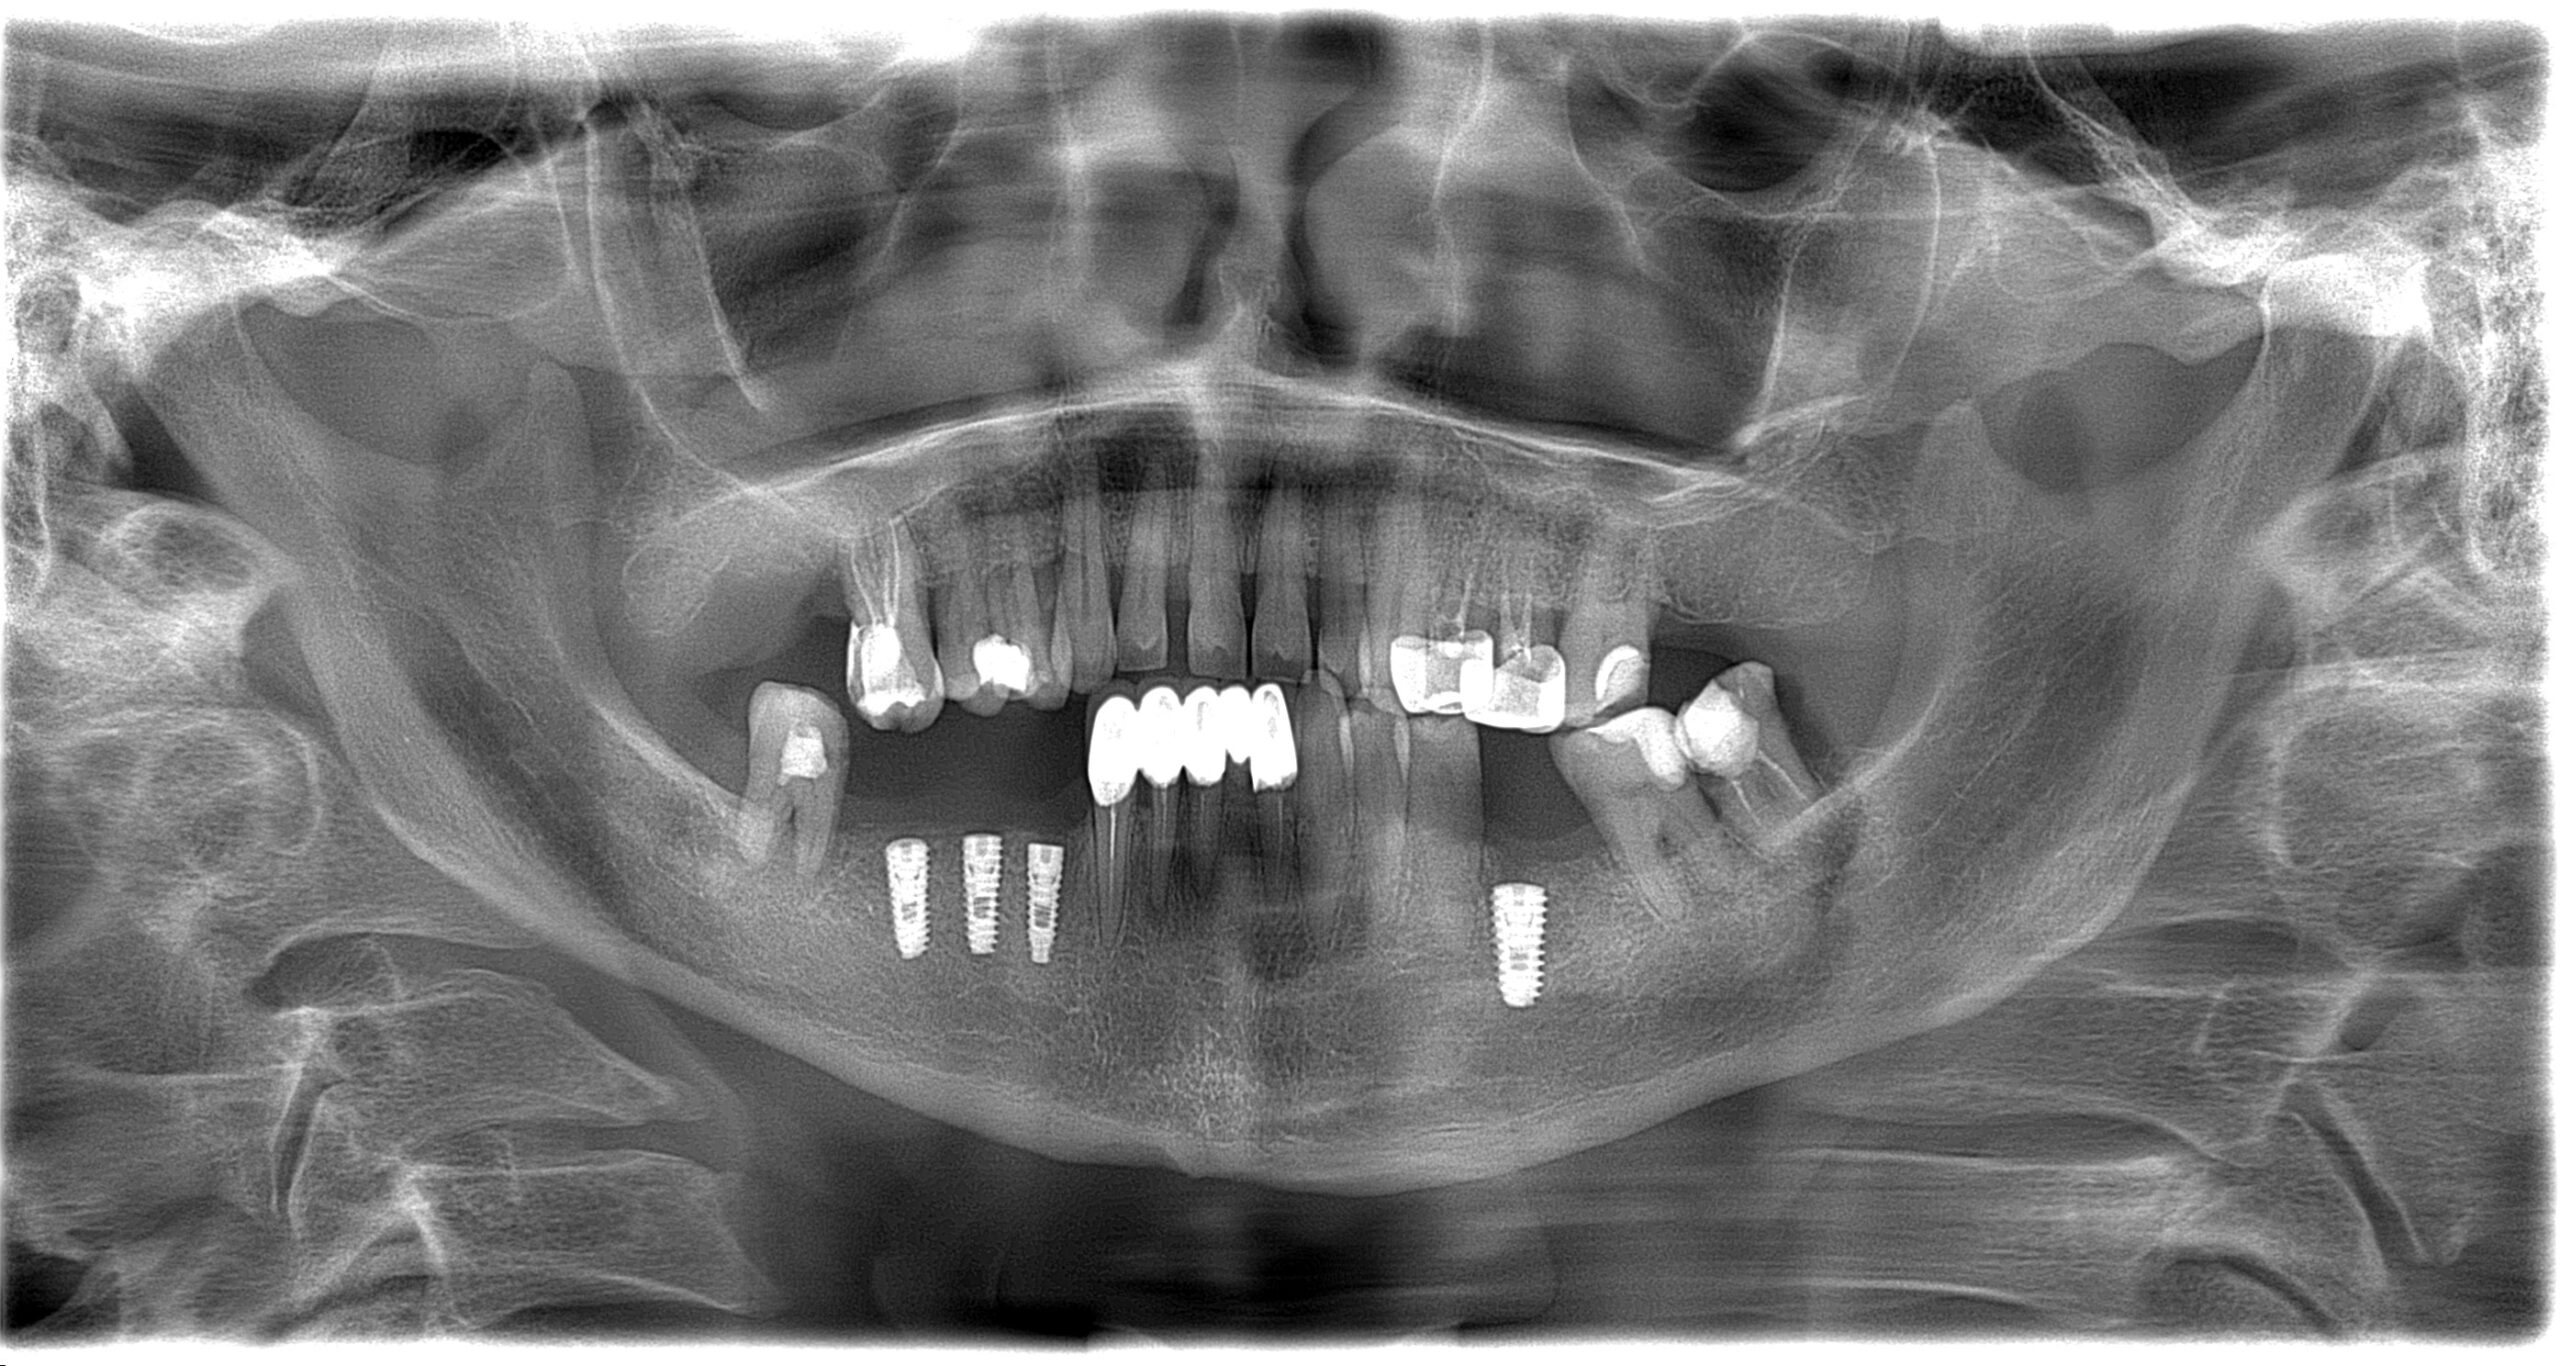

Імплантація